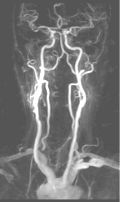

Contrast-Enhanced Subtraction MR Angiography (CE-MRA): State-of-the-art

CE-MRA of the aortic arch and great vessels (left) into the brain, renal arteries (top), selective carotid bifurcation (top right) showing ICA/ECA stenosis, and 3-section run-off (very right) showing multiple stenoses, including long-segment bilateral SFA stenoses.